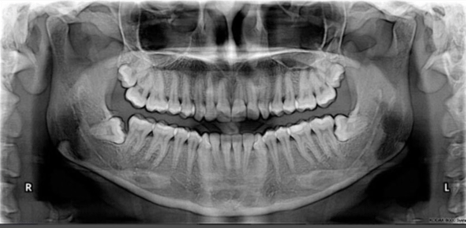

En este video la Dra. Lugo explica las distintas características a evaluar en lesiones para diferenciar aquellas que sugieran Benignidad de Malignidad, como lo son: Tipo de imagen Bordes Tamaño Relación con la cortical adyacente Relación con los dientes adyacentes entre otras. Material de apoyo: Cátedra de Radiología de la Facultad de Odontología de la […]